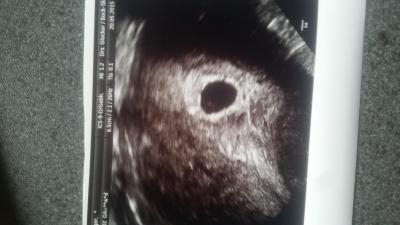

Ich komme grad vom FA und weiss nicht was ich von all dem halten soll. :( sie meinte zwar, alles gut, aber 6+1 und kein Herzschlag macht mir Angst. Anbei das Bild. Die FH ist richtig gut gewachsen und den Dottetsack mit Embryo sieht man heute auch. Was denkt ihr?

Bild zu 6+1 kein Herzschlag.... - Schwanger - wer noch? Rund um die Schwangerschaft

Fruchthöhle sieht doch schön aus und es ist nicht ungewöhnlich zu der Zeit keinen Herzschlag zu sehen. Entsannt bleiben! Wann hast du wieder termln?